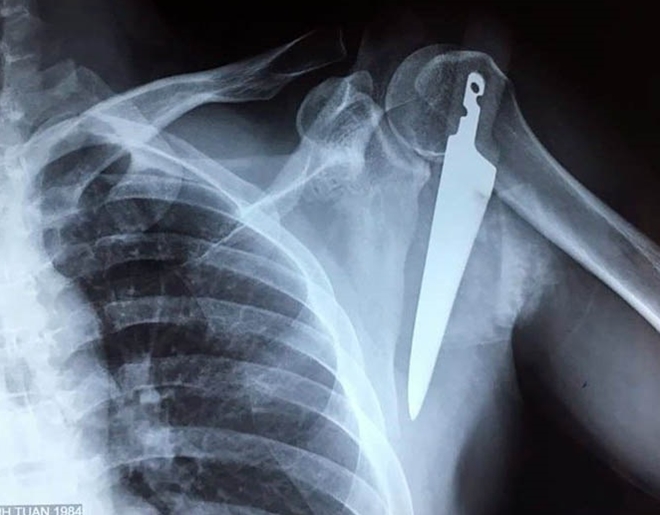

Cứu bệnh nhân bị dao dài 20cm cắm vào vai

Ngày 14-2, Bệnh viện Việt Nam-Thụy Điển Uông Bí (Quảng Ninh) cho biết vừa cấp cứu thành công bệnh nhân ngã trong bếp bị con dao sắc, nhọn dài khoảng 20cm cắm vào vai.

Trước đó, ngày 8-2, anh L.T.T (35 tuổi, trú tại TP Uông Bí, Quảng Ninh) nhập viện trong tình trạng có một con dao găm sâu vào vai trái ngay 1/3 giữa dưới xương đòn, chảy nhiều máu. Vị trí này gần ngay các động mạch lớn và đám rối thần kinh cánh tay...

Phim chụp con dao đâm vào vai bệnh nhân

Các bác sĩ nhận định, nếu không được tiến hành phẫu thuật cấp cứu kịp thời sẽ gây nhiều nguy cơ cho người bệnh như chảy máu nhiều, mất máu, nhiễm trùng... và có thể tử vong. Vì thế, các bác sỹ đã khẩn trương phẫu thuật cấp cứu, lấy con dao ra khỏi vùng vai trái của bệnh nhân. Đồng thời nối cơ, xử lý vết thương cho người bệnh.

Hiện sức khỏe của anh T đã dần ổn định, vết mổ khô và sẽ được xuất viện trong vài ngày tới.